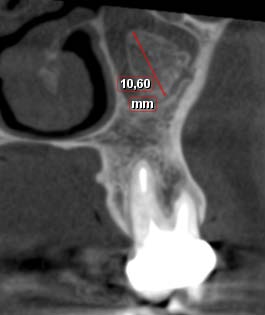

3) The location of the calcifications in the maxillary sinus: central, peripheral. 4) The number of calcifications. 5) The size of calcifications: Four proposals were chosen for this variable: Less than 1 mm, between 1 and 2 mm, between 2 and 5 mm, greater than 5 mm. The value was determined by the measurement tool at scale 1; The largest according to coronal sections. 6) Unilaterality 7) The nature of intra-sinus calcification: pathological calcifications of dental origin found in aspergillus sinusitis as a result of an overflow of dental paste, calcifications related to dental residues displaced in the sinus, and idiopathic intra-sinus calcifications incidentally found whose circumstances of occurrence are unknown. Characteristics of associated lesions:

? Thickening of Schneider's membrane: The measurement was performed between the point where the mucous thickening was maximal and the sinus floor. ? Sinus ventilation: has been evaluated by the freedom of the ostium of the maxillary sinus. ? Polyp and cyst: were determined by the presence of homogeneous, mono or poly-geodic sinus opacity with a regular contour. ? Oro-antral communication (OAC): has been determined by the sinus membrane perforation. ? Presence or not of an inflammatory process of dental origin: was determined by the presence or not of a peri-apical lesion.

Several theories are put forward. First, the ventilation of the maxillary sinus would be responsible. The ventilation of the maxillary sinus via its ostium is essential to maintain its biological balance. It was found decreased in 78% of the cases in our work. Mucus in the sinus plays a major role as a protective colloid so that the salts do not concentrate. (36) However, once the inflammation is established, sinus ventilation is impaired, sinus drainage is compromised, mucous secretions accumulate, increase PH, change the mineral environment and lead to the precipitation of calcium salts which would lead to the formation of intra-sinus calcifications. (29) Second, the formation of idiopathic calcifications of endogenous origin is linked to the osteogenic power of the Schneider membrane. Srouji et al. analyzed the osteogenic potential of the human maxillary sinus Schneider membrane using in vitro and in vivo assays. (37) Samples of the membrane were used to prepare cell cultures for histological studies. The results showed that the cells derived from these membrane extracts grow in culture and express markers of osteoprogenitor cells (alkaline phosphatase, protein 2 specific to bone morphogenesis, osteopontin, osteonectin and osteocalcin). Mineral deposits have also been found including phosphate and calcium ions. Once differentiated, these membrane-derived cells were transplanted in vivo. Therefore, histological evidence of osteogenesis has been found at the site of transplantation. The results of this study showed the presence of osteoprogenitor cells at the Schneider membrane and asserted its osteogenic potential. However, the precise location of these osteoprogenitor cells among the layers constituting the Schneider membrane was not determined. The authors have referred to the richly vascularized chorion but also to the connective tissue similar to the periosteum next to the maxillary bone. The osteogenic potential of the Schneider membrane has been approved by several authors and in several studies. (38,39) It would explain the significant success of dental implants (93.5%) placed in the atrophied maxillary posterior region; With a residual bone of 5 mm to 9 mm: these implants are placed "in a tent pole" without using bone substitutes but only by providing space for the blood clot (40). This technique eliminates the high cost of bone substitutes but also reduces the risk of post-operative complications related to bone grafting (41). Indeed Schneider's membrane plays the role of framework for the multiplication of bone cells and their maturation (42). More studies are needed to be able to predict bone formation by focusing on the individual potential of each patient. (40) The thickness of the sinus mucosa was measured in several studies. In the present study, thickening of the sinus mucosa was reported when the thickness of the mucosa was greater than 1 mm. (FIG. 6). Its prevalence was 88.9%. Other studies have reported a prevalence ranging from 48.4% to 66% (2.8). This difference may indicate that the presence of intrasinus calcification is a contributing factor to the thickening of the sinus mucosa. It should be noted, however, that athickening of the sinus mucosa is not necessarily a sign of pathology. Allergic reactions and smoking are factors correlated with an increase in the thickness of the sinus mucosa. (43) Antral polyps are the most common benign pathologies of the maxillary sinus. Their prevalence varies between 1. 4% and 25% (2,8). Our study found a prevalence of 44%. This high frequency would indicate a relationship between the presence of antral polyps and intra-sinus calcifications.